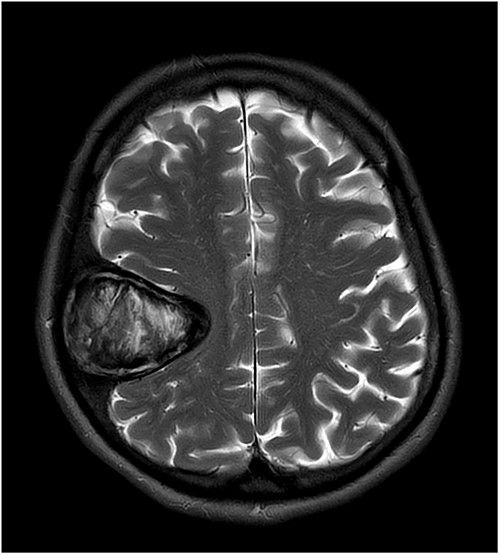

Our patient is a 76-year-old gentleman with medical history of hypertension and lumbar spondylosis. He did not have any previous history of trauma or systemic infections. He had presented to his local hospital with a 2-day history of left arm numbness. He did not report any headaches or giddiness. On clinical assessment, he did not have any neurological deficits. A CT brain and MRI brain (Figs 1–5) with contrast revealed a 53 × 53 × 41 mm partially calcified, heterogeneously enhancing conical shaped right extra-axial parietal convexity lesion. The overlying calvarial bone was remodelled and possibly eroded. There was evidence of prior haemorrhage within the lesion and scattered internal and peripheral calcification. Based on these characteristics, the possible diagnoses were that of an intraosseous meningioma, haemangioma and giant cell tumour. Patient was consented for craniotomy and excision of the tumour.

T1-weighted contrast-enhanced coronal MRI scan showing the lesion with intralesional haemorrhagic products. There is no evidence of dural invasion.